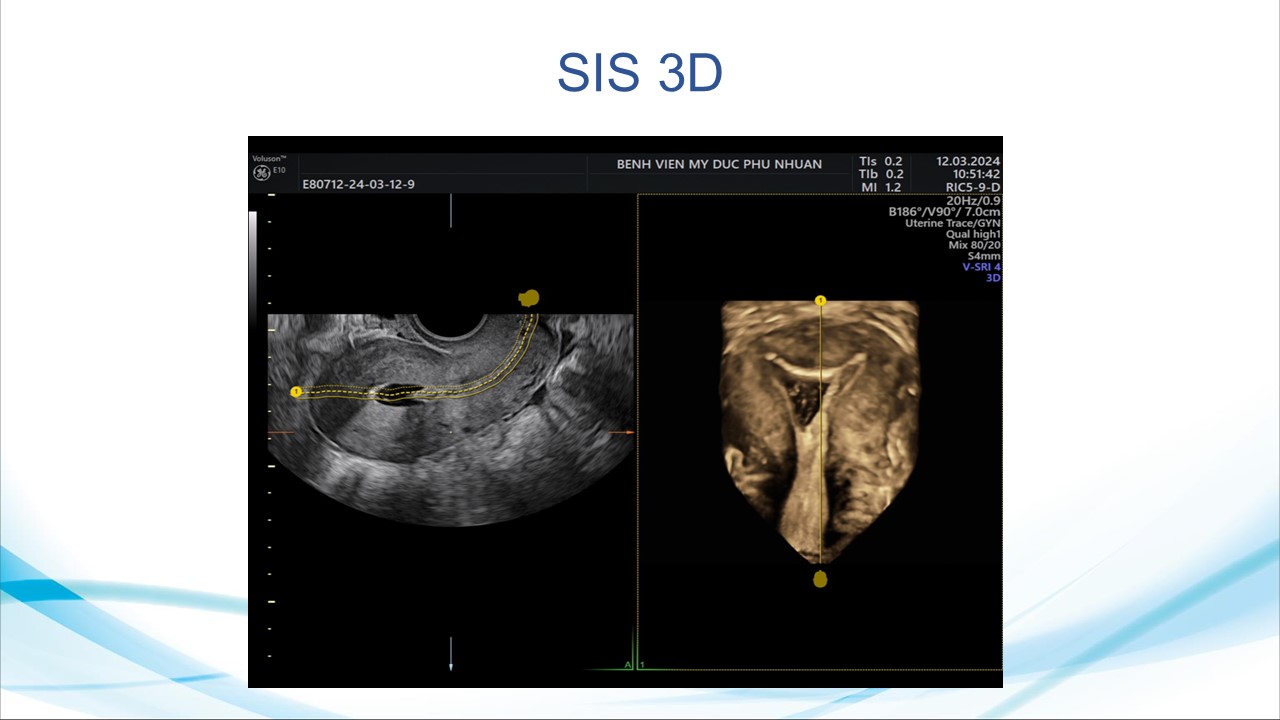

Siêu âm sử dụng chật tương phản trong phụ khoa